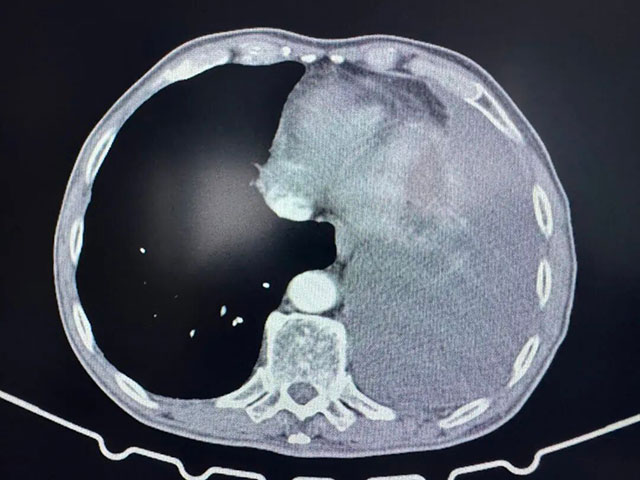

術(shù)后胸部CT

7月9日,劉浩副教授手術(shù)團隊為張爺爺實施胸腔鏡下肺部分切除術(shù)+胸腔積液清除術(shù)+胸膜活檢,成功切除了1.5×1.1×1.0cm大小的浸潤性腺癌病灶,并清除了胸腔內(nèi)積液。術(shù)后病理提示,腫瘤已侵犯肺膜,屬于晚期肺癌,治療預(yù)后不佳。